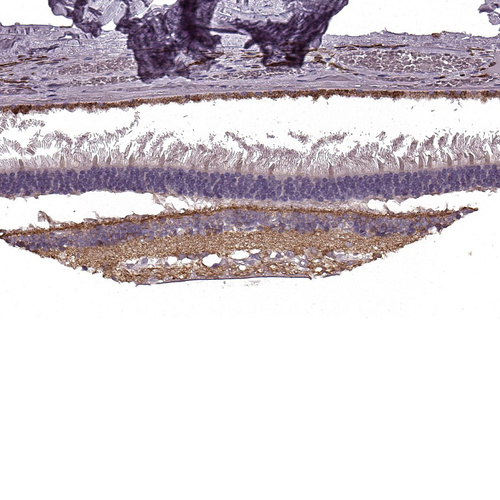

Immunohistochemical staining of human retina shows strong cytoplasmic positivity in nerve fibers.